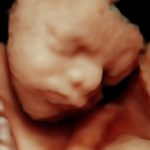

4D/5D/HD Ultrasound Gallery

Gallery